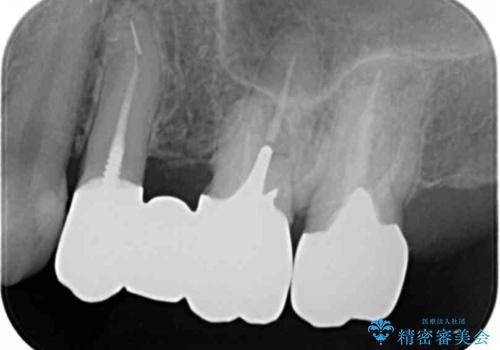

銀歯を除去し、土台の歯にに虫歯がないかを確認します。

今回は目立つ虫歯がなかったため、形を整えて白い被せものを装着しました。